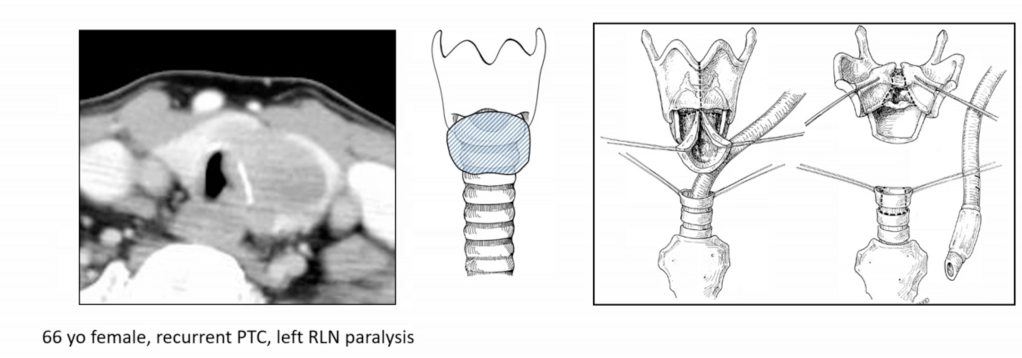

- Recurrent Laryngeal Nerve (RLN):

- If non-functional or fully invaded:

- Resection is advised with or without reinnervation techniques

- Postoperative vocal cord assessment is mandatory

- Statement 2-A:

- RLN encased, ipsilateral vocal cord (VC) paresis / paralysis:

- Resection is indicated (consensus)

- If the nerve is sacrified RLN reconstruction is advisable or thyroplasty or cord injection.